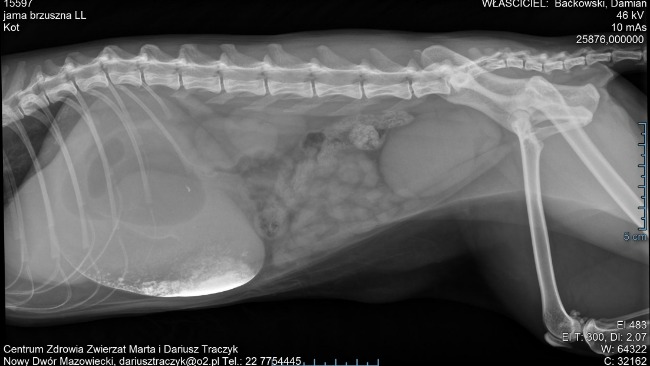

Moja 4,5-letnia kotka przeszła pilną operację ratującą życie z powodu niedrożności przewodu pokarmowego.

W dwunastnicy znajdował się fragment pianki (jak z tanich mat do ćwiczeń), który całkowicie zablokował pasaż. Zabieg musiał zostać wykonany natychmiast — liczyły się godziny.